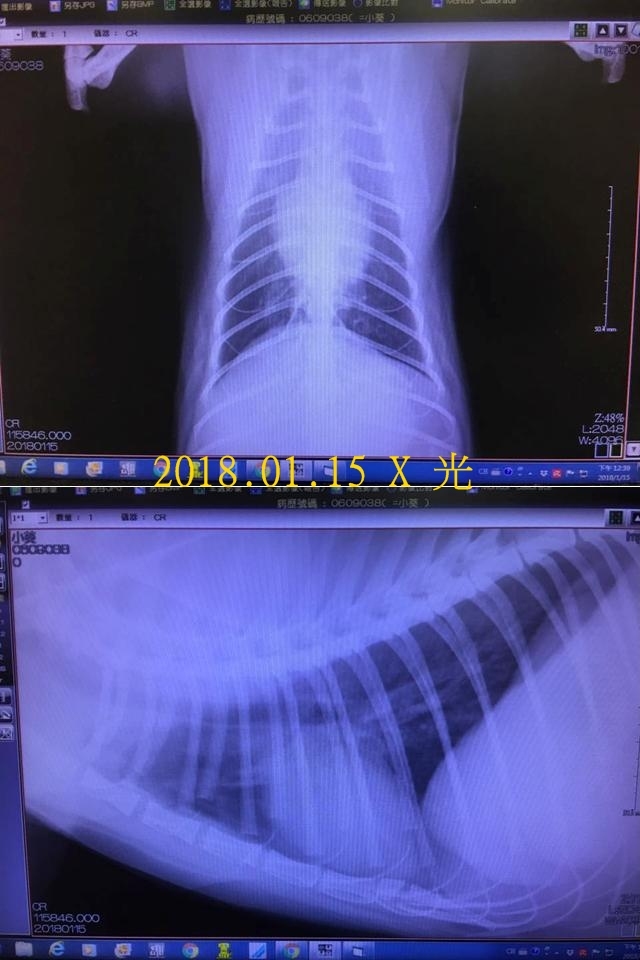

2017年12月時因小葵呼吸聲很大,帶她至醫院看診,拍胸腔x光片發現肺部有輕微發炎,除了需要服用藥物,還要每天做兩次的氣霧治療,並持續回診檢查治療情況,請大家幫忙小葵的醫療費用。

抽血結果顯示其他都正常只有球蛋白偏高,但還在可接受範圍;拍胸腔X光看到肺臟狀況有好很多,醫師這次會把類固醇加回去但是「三天」吃一次,噴霧仍然繼續噴

動物近況說明: 持續幾週的醫療後,小葵已沒有那麼大的呼吸聲了,X光檢查肺部也已無發炎情況,癒後的小葵食慾變得很好,越來越有活力,每天都開心的吃飯玩耍。